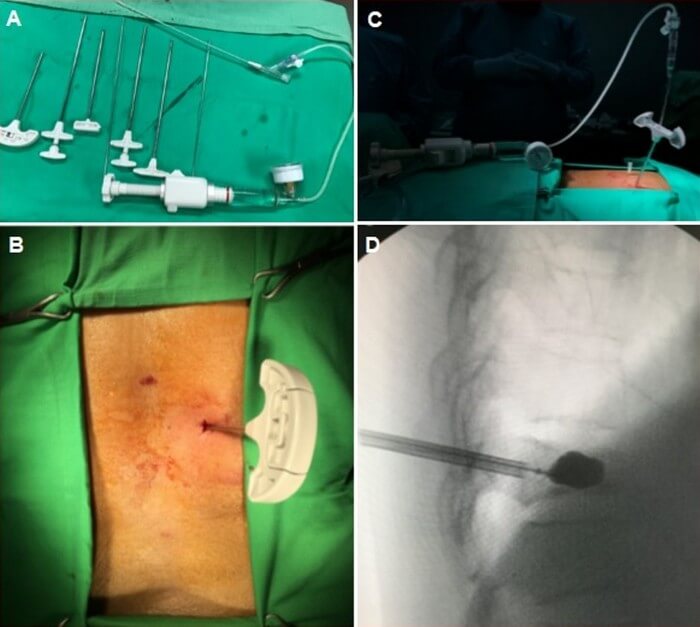

Η κυφοπλαστική είναι η πλέον σύγχρονη μέθοδος αντιμετώπισης των οστεοπορωτικών καταγμάτων της σπονδυλικής στήλης. Κατά την επέμβαση, ο ορθοπαιδικός χειρουργός, με ακτινοσκοπική καθοδήγηση, εισάγει διαδερμικά (με δύο μικρές τρυπούλες) στον σπόνδυλο μια μικρή συσκευή σαν μπαλονάκι, το οποίο φουσκώνει και αποκαθιστά τον σπόνδυλο, επαναφέροντάς τον στο αρχικό του σχήμα και θέση. Έπειτα, ξεφουσκώνει το μπαλονάκι και γεμίζει το κενό που έχει δημιουργηθεί με ειδικό οστικό τσιμέντο, σταθεροποιώντας τον σπόνδυλο.

Για κάθε σπόνδυλο απαιτούνται περίπου 30 λεπτά, η επέμβαση γίνεται με τοπική αναισθησία ή ήπια καταστολή (μέθη), είναι εντελώς αναίμακτη και ο ασθενής μπορεί μετά από λίγες ώρες να επιστρέψει στο σπίτι του και στις καθημερινές του δραστηριότητες.

Η κυφοπλαστική θεωρείται η πλέον ασφαλής και αποτελεσματική μέθοδος χειρουργικής αντιμετώπισης τέτοιου είδους καταγμάτων η οποία, μιας και αποτελεί μια ελάχιστα επεμβατική τεχνική, έχει πολύ πιο σύντομη διάρκεια αλλά και πολύ μικρότερη απώλεια αίματος από την παλαιότερη μέθοδο της σπονδυλοδεσίας.